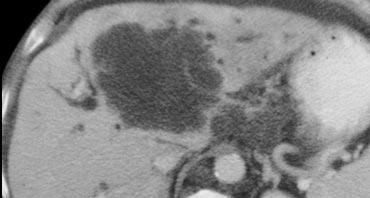

U máu khổng lồ có mô sẹo. Lưu ý mức độ ngấm thuốc tương đương hồ máu ở tất cả các thì. Sẹo trung tâm giảm tỷ trọng trên NECT và vẫn giảm tỷ trọng ở các thì sau.